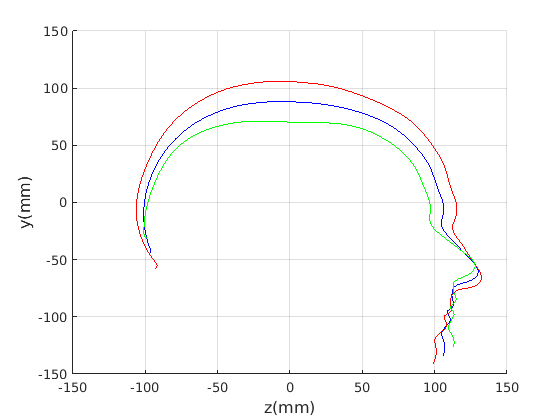

6.2 Model compactness

We evaluate both model construction with geometric alignment (ECN normalisation) and model construction with alignment by Generalised Procrustes Analysis (GPA). Model compactness is a key performance criterion for the correspondence and alignment processes that generate that model [31]. A more compact model has a smaller variance and requires fewer parameters to express a particular shape instance than less compact model. Cumulative variance plots generated by application of PCA are a useful measure of compactness, with more rapidly rising curves indicating more compact models. In Fig. 23 and Fig. 24 we present the cumulative variance plots for our profile models using automatic and manual landmarking respectively and aligned with either ECN or GPA alignment schemes.

Comparing the compactness of the models produced by automatic and manual facial profile landmarking, we found that the performance is almost identical and there is no statistical significance in performance given the modest test size of 100 faces. For example, for the full head profile, with no scale normalisation, the automatic landmarks give cumulative variances of 51.5%, 76.5%, 88.9% and 91.3% over the first four modes whereas the manual landmarks give 50.8%, 76.5%, 88.9% and 91.2%.

A point to note is that whatever model is built, ECN always produces more compact models than GPA. The difference is more marked when a head model is built (cranium and face) compared to cranium only. This can be explained by the fact that the cranium has 210 points sampled on its surface, whereas the face has 128. ECN focusses on aligning the majority group (cranial points) and does not allow more extreme features (such as a large nose) to influence this. GPA on the other hand does, so relatively few points around the nose region can influence alignment over the whole cranium. ECN normalisation is more appropriate when we are interested in cranial shape.